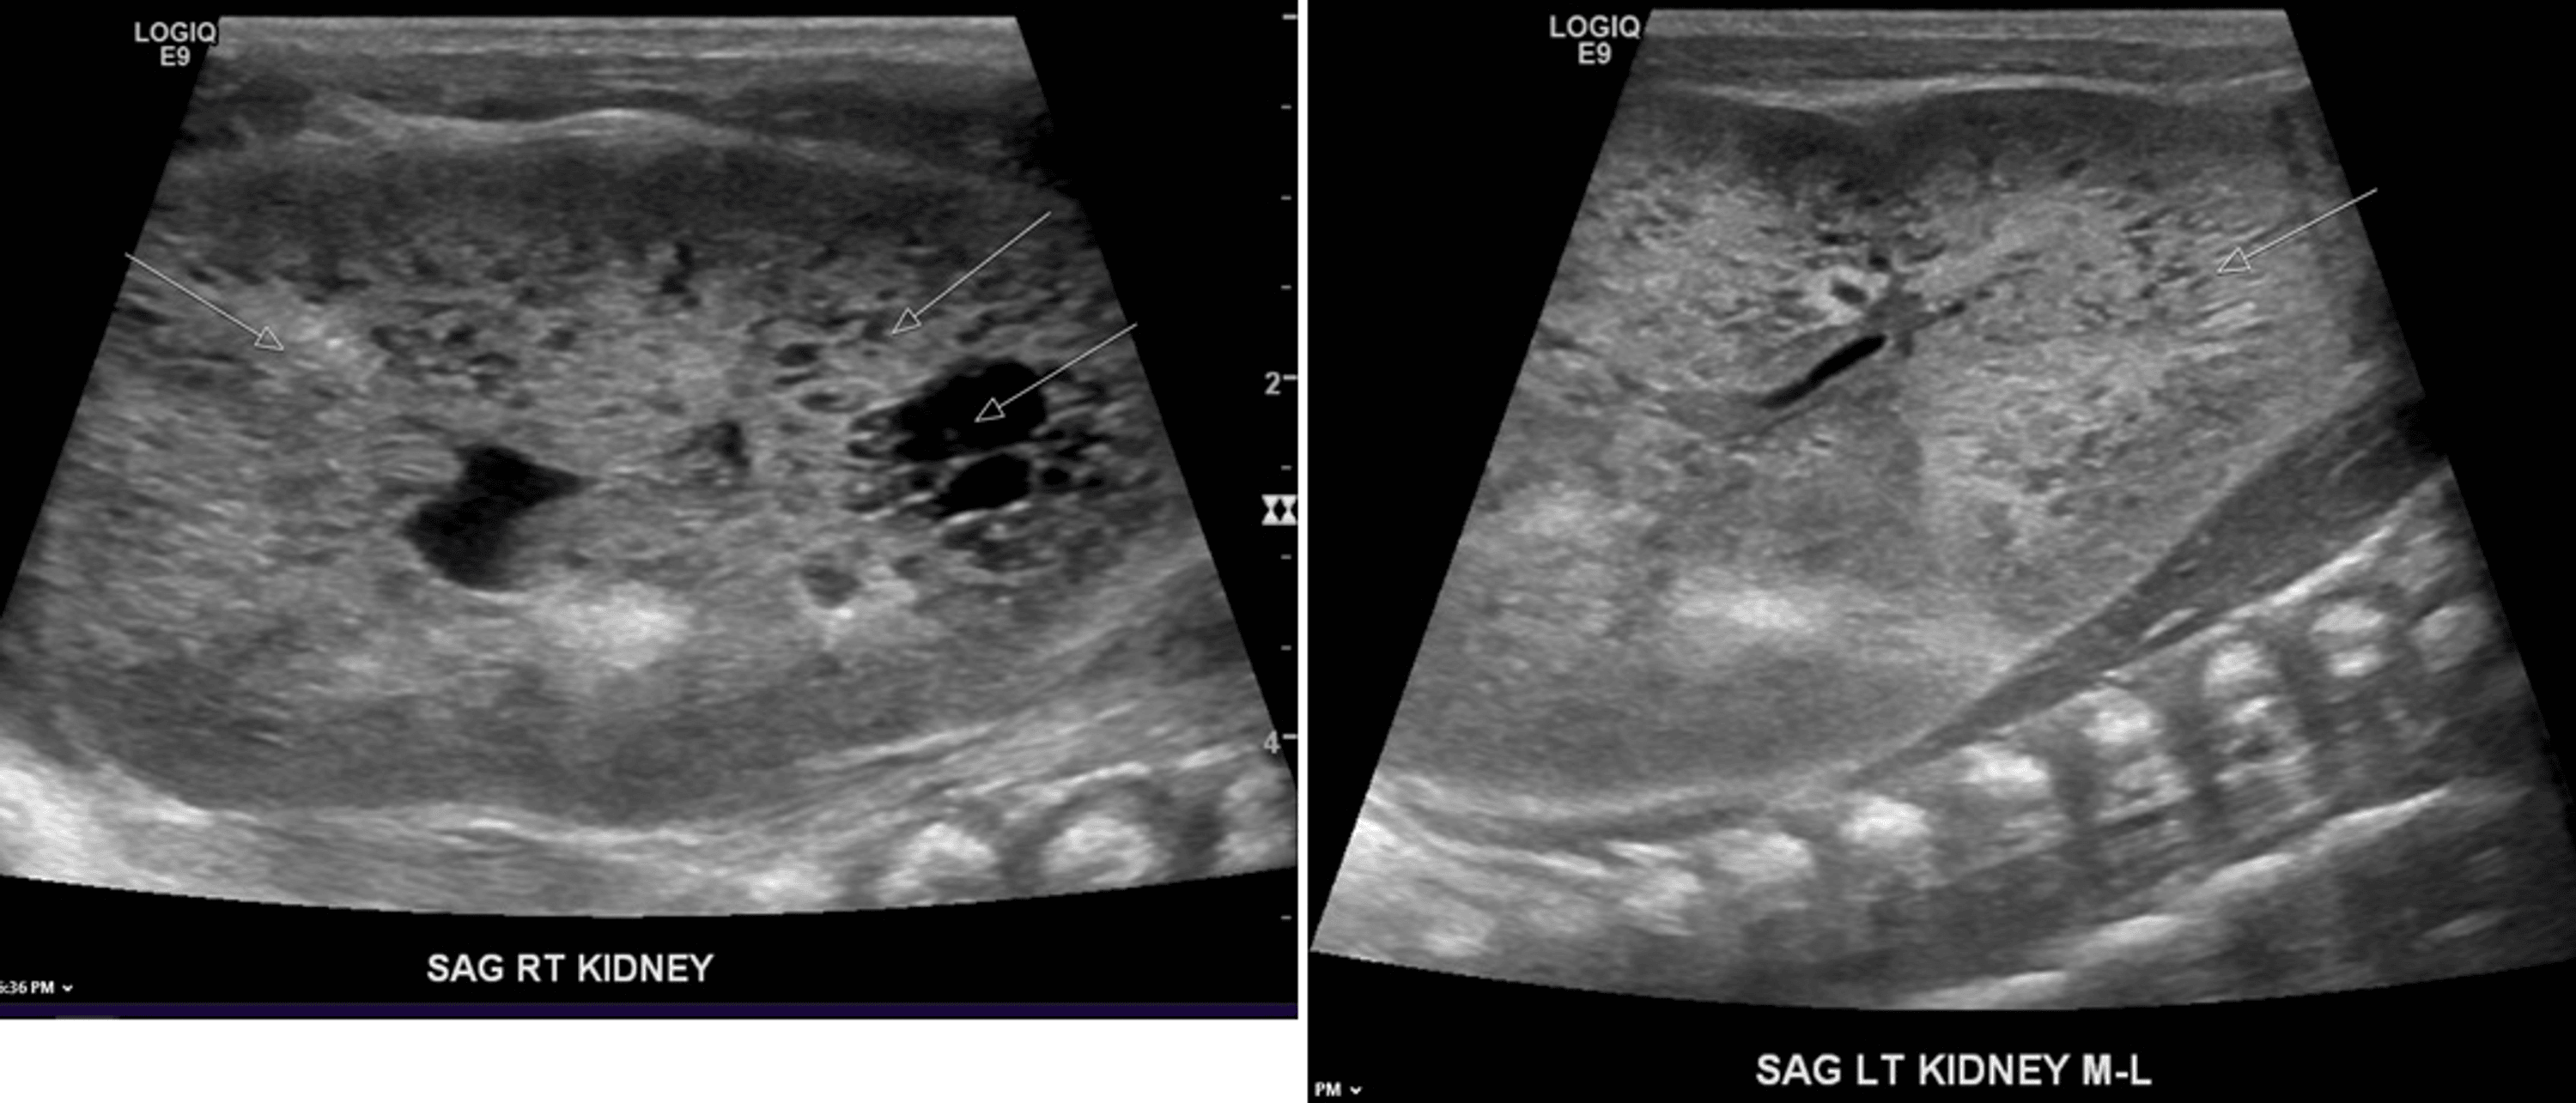

From www.wjgnet.com

Point of care renal ultrasonography for the busy nephrologist A Sponge Kidney In Neonates What is medullary sponge kidney? Medullary sponge kidney is a congenital disorder meaning you're born with it. Anatomically it is characterized by cystic dilatation of the renal. Medullary sponge kidney is a benign congenital abnormality that was first described in 1939. Medullary sponge kidney (msk) is a congenital disorder, meaning it is present at birth. Medullary sponge kidney associated with. Sponge Kidney In Neonates.